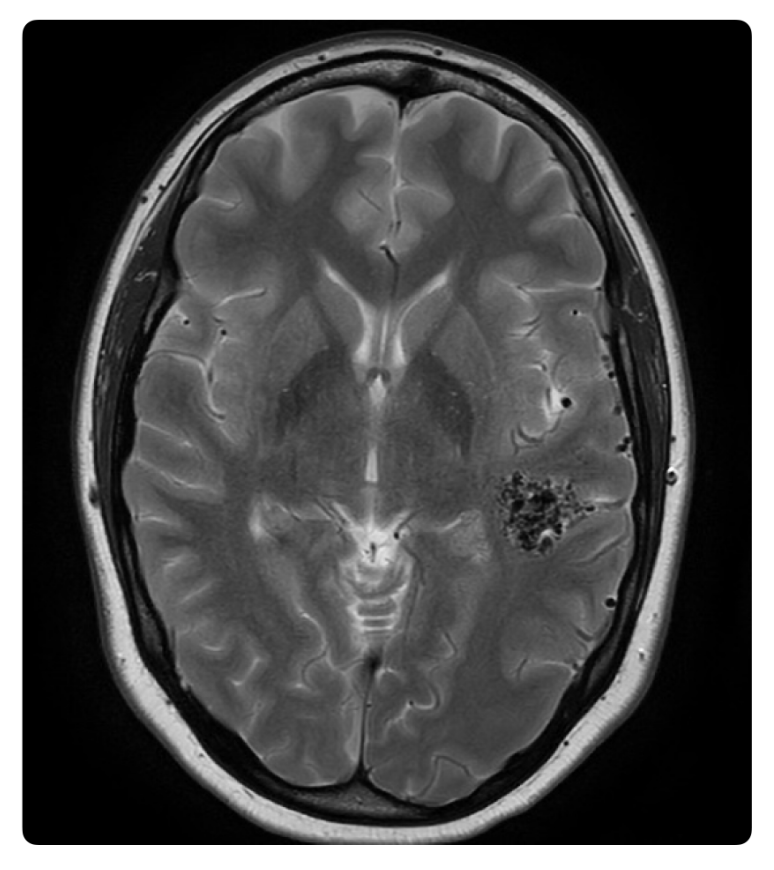

What dx?

A

Arteriovenous malformations (AVMs